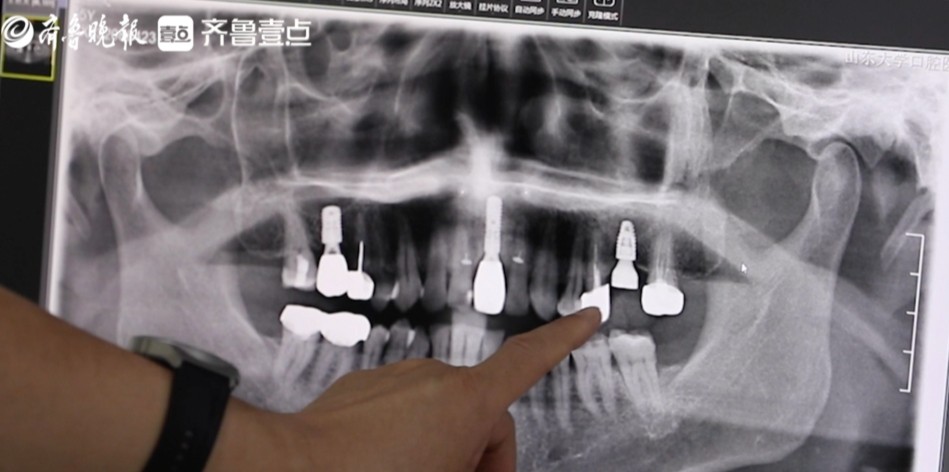

在多次前往各大医院接受消炎治疗后,症状始终未能得到根治。2022年末,他选择前往省口腔医院寻求更专业的治疗建议。经过详细检查,医生告知王先生,由于牙齿损坏严重,建议拔除并进行种植牙手术。面对这一建议,王先生心中虽有不舍,但考虑到门牙的美容功能,他最终接受了医生的建议。

然而,高昂的种植牙费用却让王先生一度犹豫不决。经过多方打听,他得知种植牙手术费用高达1.5万元左右,这让他感到颇为排斥。“说实话,这个价格对老百姓来说,有点昂贵,我有点舍不得。”但经过深思熟虑,王世文还是决定为了恢复牙齿健康和美观,承担这笔费用。半年后,王世文成功种上了新牙,不仅牙齿恢复了美观,使用体验也极佳。他感慨:“牙齿的质量非常可靠,因为是门牙,我选择了医院最好的品牌,除了贵别的体验都很好!”

“门牙种了之后体验感很好,我就想把之前镶的两颗大牙也换成种植牙。”王世文说。在得知集采政策后,他毫不犹豫地种了两颗大牙。这也是王世文从被动种植牙到主动种植牙的转变。“原来种一颗牙要花1万5,现在同样的品牌材质,种一颗牙才花一半的钱,经济压力下降很多,太好了!”他告诉记者。